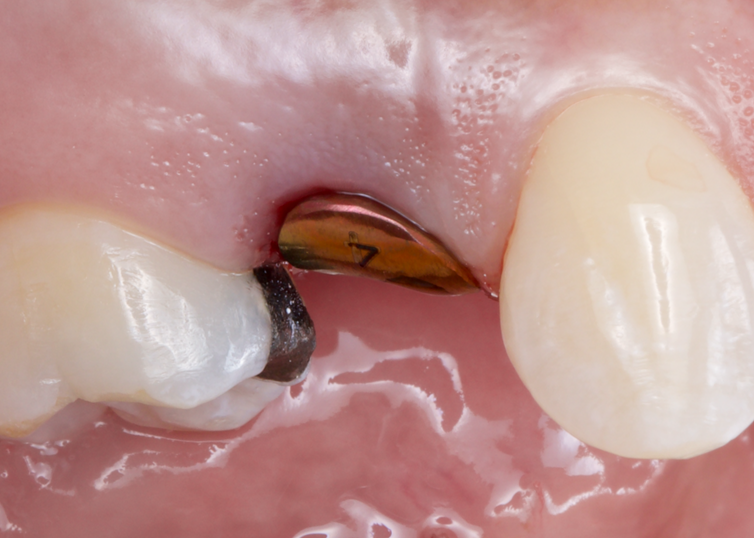

This comprehensive one-day course bridges the gap between implant placement and prosthetic restoration, focusing on the clinical and technical aspects of restoring dental implants in modern practice. Participants will gain practical knowledge in both analog and digital workflows, with emphasis on single-unit restorations while exploring multiple implant and full-arch rehabilitation protocols. The course includes a hands-on component where participants will practice digital scanning with an intraoral scanner and review the delivery considerations for screw-retained versus screw-mentable restorations.

Participants will learn to navigate the decision-making process between traditional and digital workflows, master impression techniques for various clinical scenarios, and understand the integration of CAD/CAM technology in implant dentistry.